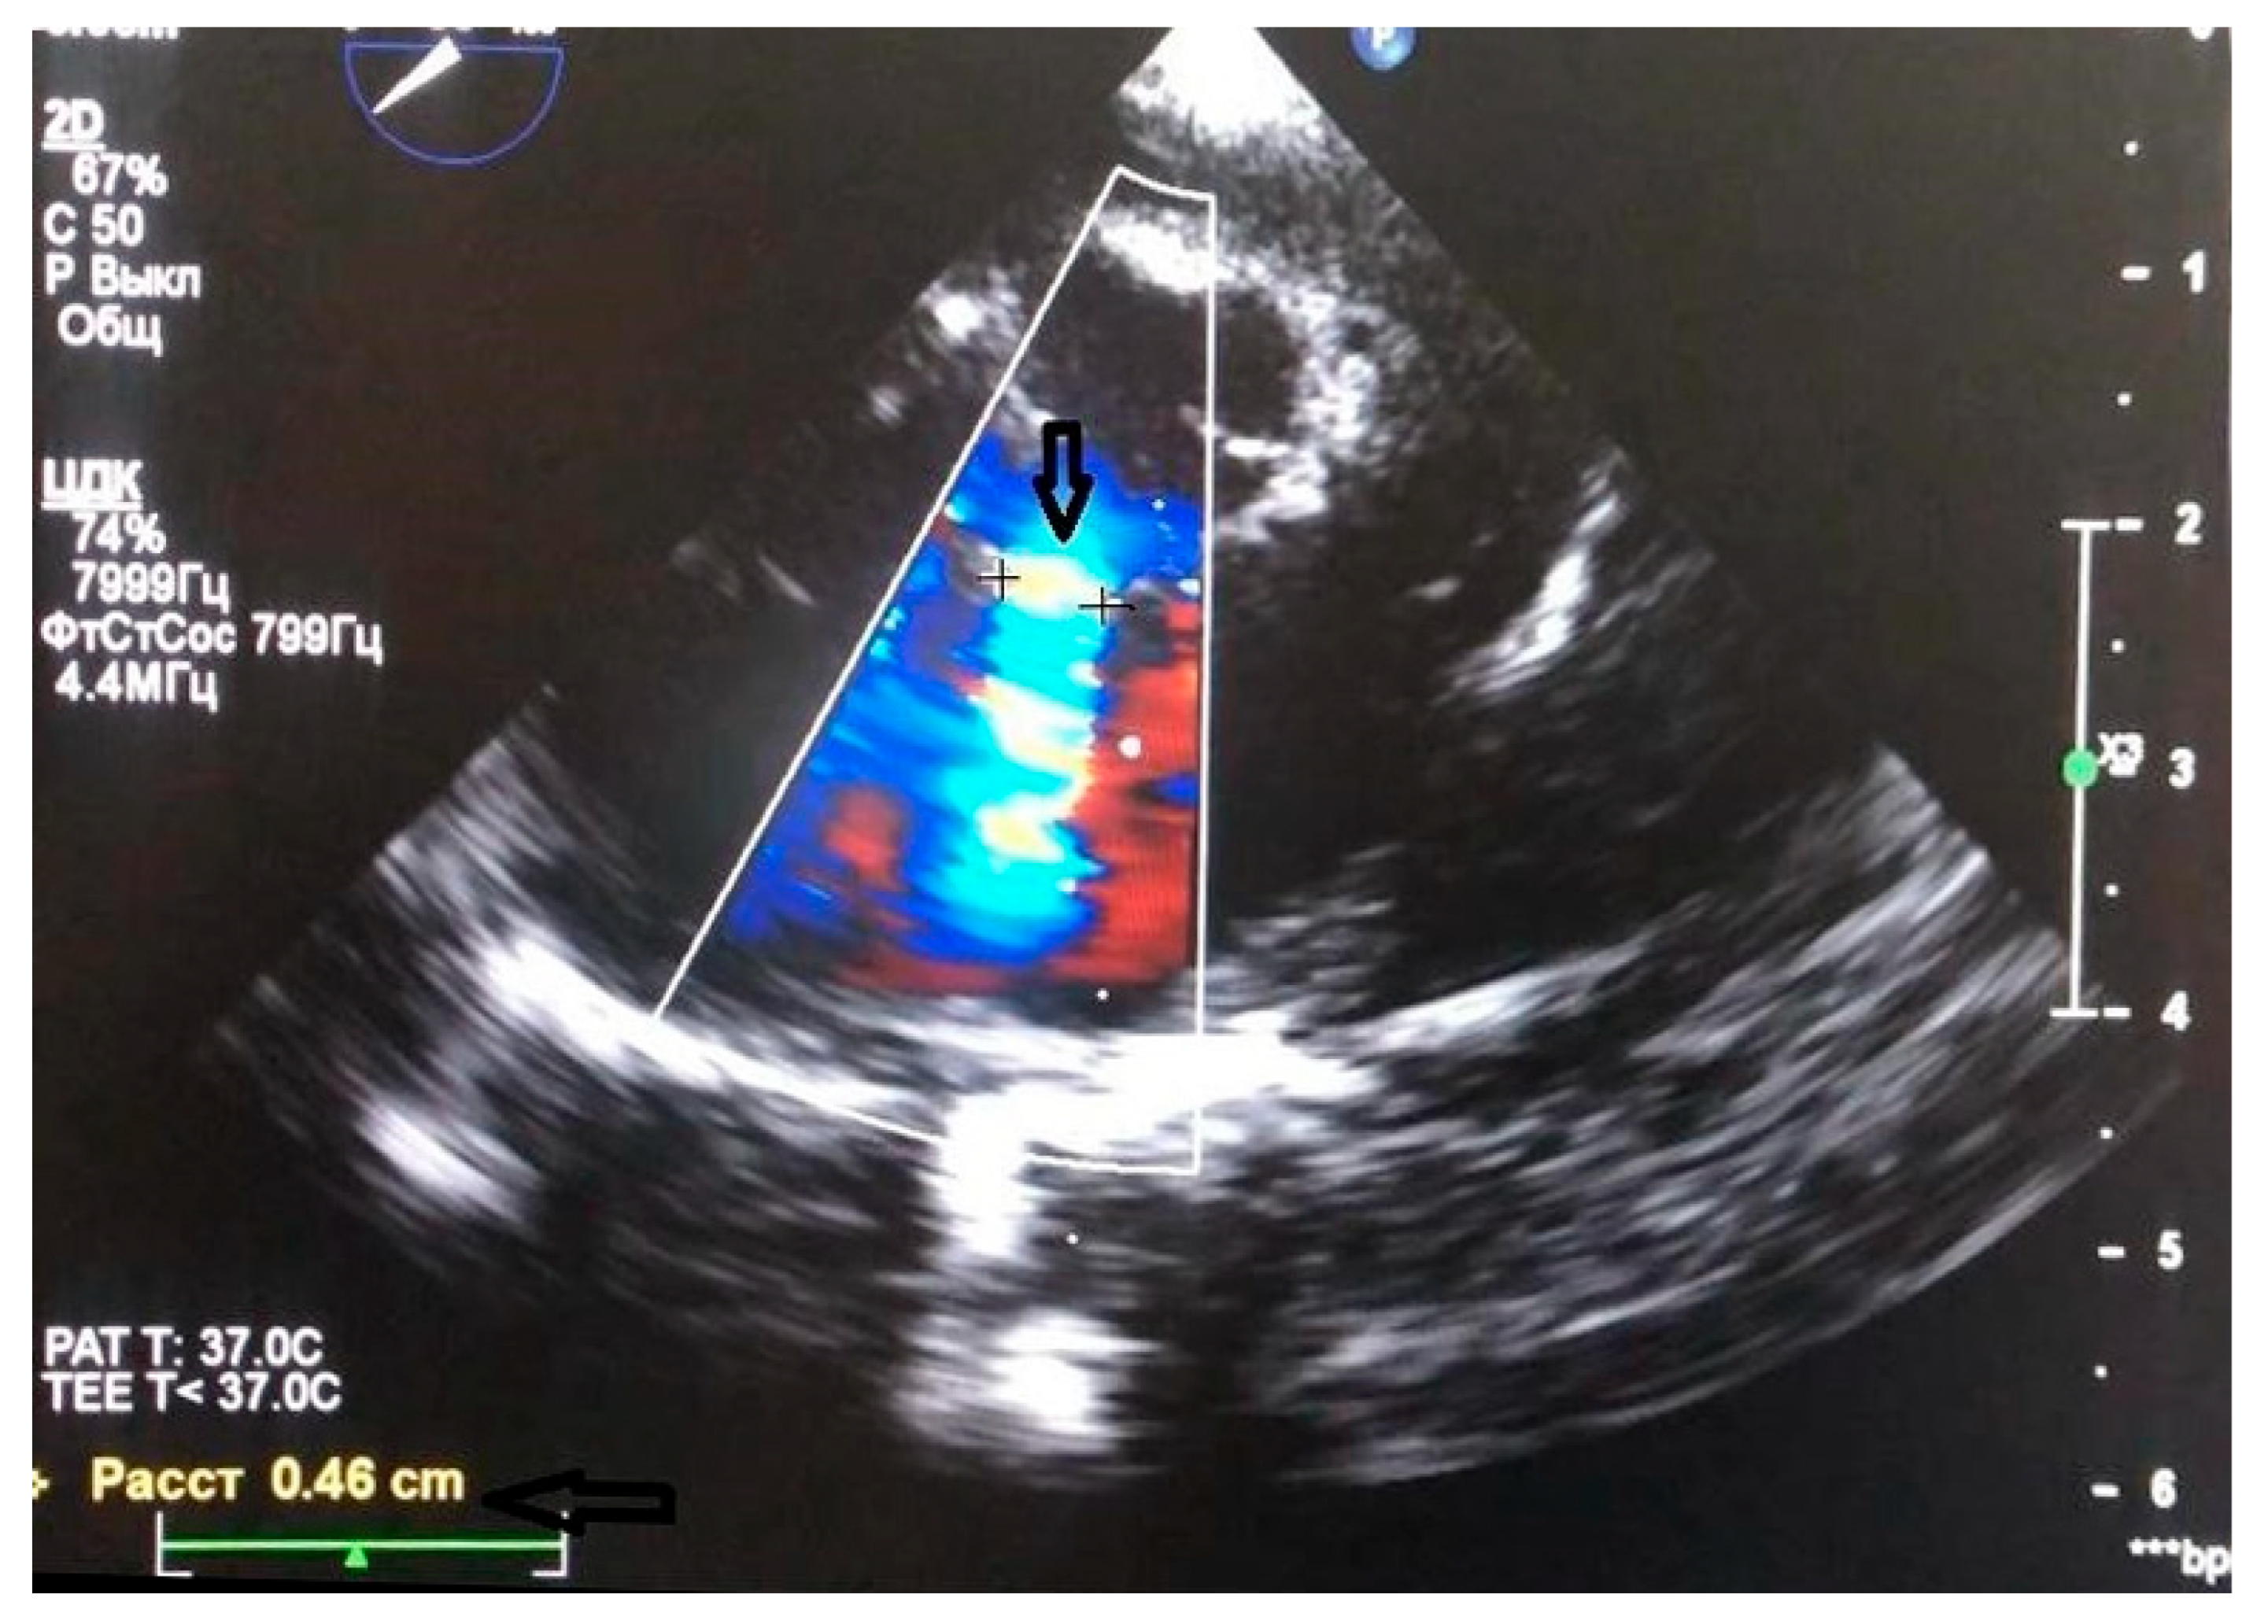

- Huang, L.L.; Chen, M.; Zeng, C.; Su, C.X.; Jiang, C.L.; Zheng, B.S.; Wu, J.; Li, S.K. Comparison of perventricular and percutaneous ultrasound-guided device closure of perimembranous ventricular septal defects. Front Cardiovasc Med 2023, 10, 1281860. [Google Scholar] [CrossRef]